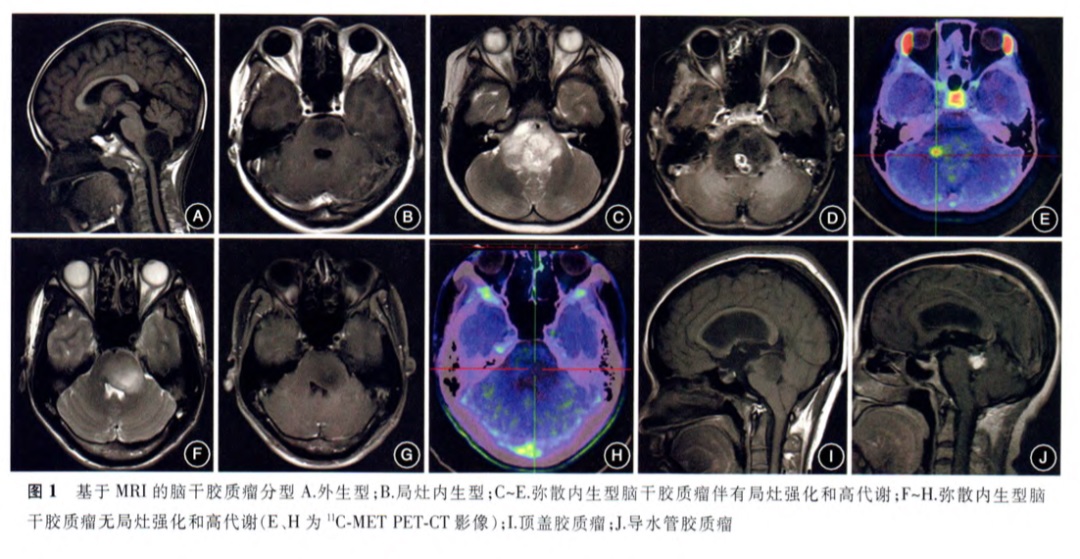

图1.基于MRI的脑干胶质瘤分型A.外生型;B.局灶内生型;C-E.弥散内生型脑干胶质瘤伴有局灶强化和高代谢;F-H.弥散内生型脑干胶质瘤无局灶强化和高代谢(C、H为11C-METPET-CT影像);I.顶盖胶质瘤;J.导水管胶质瘤.不同型治疗或预后会有差别。图自脑干胶质瘤咨询共识

其实,脑干桥脑位置除了DIPG外,还有背侧外生型脑桥胶质瘤等。脑干肿瘤是跨越脑干中脑、脑桥、延髓区域并可压迫小脑、颈髓等的一组异质性肿瘤,脑干肿瘤占儿童颅内肿瘤的10%-20%,占成人颅内肿瘤的1.5%~2.5%,脑干胶质瘤是较常见的病理类型,其他包括海绵状血管瘤、转移瘤、成血管细胞瘤、淋巴瘤等。

脑桥肿瘤:儿童脑桥肿瘤通常是恶性程度不同的胶质瘤,主要分为弥漫性内生性脑桥胶质瘤(DIPG)、背侧外生或局灶性脑桥肿瘤,主要基于神经放射学表现。在这里,我们将主要介绍DIPG和背侧外生性脑桥胶质瘤。